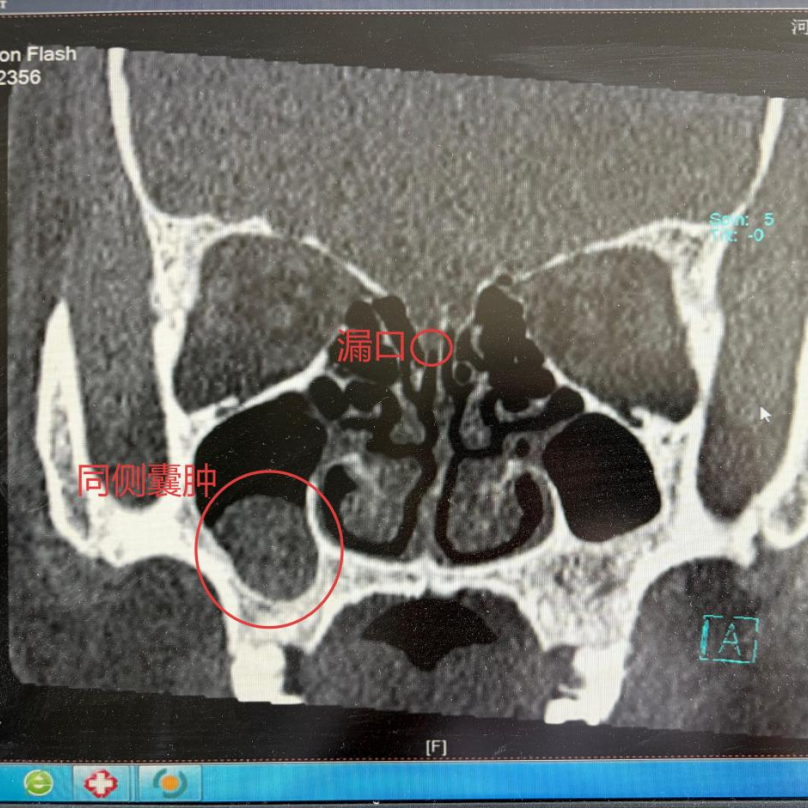

该患者以单侧鼻腔持续流出清亮液体为主诉,初期自行按感冒和鼻炎治疗无效。外院鼻窦 CT 曾提示同侧上颌窦囊肿,考虑可能为上颌窦囊肿破裂后流出的囊液。

得益于鼻内镜技术的进步,此类手术已告别传统开颅的「大刀阔斧」。患者在鼻内镜引导下,精准定位到右侧筛板一处直径约 6 mm 的漏口,医生巧妙取用患者自身鼻腔黏膜瓣,成功修补漏点。